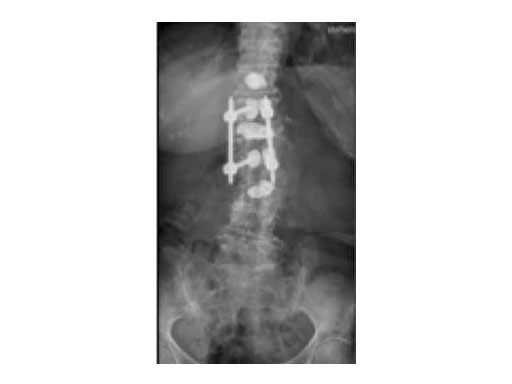

Synflate can be used stand-alone or in combination with posterior instrumentation (see the clinical cases within this article).

A 78-year-old woman was affected by steroid induced osteoporosis. She had persisting pain (mechanic and muscular) due to static imbalance (hyperkyphosis) and nonunion 8 months after a minor trauma with a vertebral compression fracture and vertebra plana of L1, and development of symptomatic stenosis of the spinal canal with loss of mobility over time. Pre-existing degenerative lumbar scoliosis was increased by the fracture.